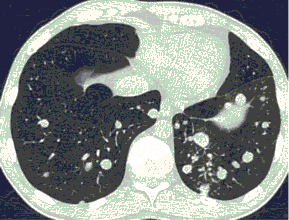

КТ имеет высокую чувствительность в выявлении изменений в легких, характерных для COVID-19. Применение КТ целесообразно для первичной оценки состояния ОГК у пациентов с тяжелыми прогрессирующими формами заболевания, а также для дифференциальной диагностики выявленных изменений и оценки динамики процесса. КТ позволяет выявить характерные изменения в легких у пациентов с COVID-19 еще до появления положительных лабораторных тестов на инфекцию с помощью МАНК. В то же время, КТ выявляет изменения легких у значительного числа пациентов с бессимптомной и легкой формами заболевания, которым не требуется госпитализация. Результаты КТ в этих случаях не влияют на тактику лечения и прогноз заболевания при наличии лабораторного подтверждения COVID-19. Поэтому массовое применение КТ для скрининга асимптомных и легких форм болезни не рекомендуется. При первичном обращении пациента с подозрением на COVID-19 рекомендуется назначать КТ только при наличии клинических и инструментальных признаков дыхательной недостаточности (SpO2 < 95%, ЧДД > 22).

3. Применение лучевых методов у пациентов с симптомами ОРВИ легкой степени тяжести и стабильном состоянии пациента, возможно только по конкретным клиническим показаниям, в том числе при наличии факторов риска, при условии достаточных технических и организационных возможностей. Методом выбора в этом случае является КТ легких по стандартному протоколу без внутривенного контрастирования или РГ при ограниченной доступности КТ. Использование УЗИ в этих случаях нецелесообразно. Применение КТ исследования в сроки ранее 3 - 5 дней с момента появления симптомов заболевания, а также при отсутствии клинических проявлений поражения бронхолегочной системы является нецелесообразным. Выполнение КТ целесообразно при наличии клинических и инструментальных признаков дыхательной недостаточности (SpO2 < 95%, ЧДД > 22), либо при дифференциальной диагностике с другим заболеванием.

4. Все выявляемые при лучевых исследованиях признаки, включая КТ-симптомы, не являются специфичными для какого-либо вида инфекции и не позволяют установить этиологический диагноз. Вне клинической (эпидемической) ситуации они не позволяют отнести выявленные изменения к пневмонии COVID-19 и дифференцировать их с другими пневмониями и невоспалительными заболеваниями. Данные лучевого исследования не заменяют результаты обследования на РНК SARS-CoV-2. Отсутствие изменений при КТ не исключают наличие COVID-19 и возможность развития пневмонии после проведения исследования.